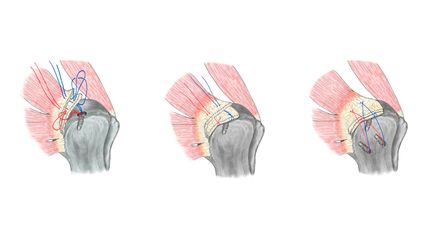

Operationstechniken, Patienten-selektion und Einfluss von Alter

Die heutigen Operationstechniken der medialen Meniskusrefixation umfassen vor allem All-inside-, Inside-out- und transtibiale Verfahren, die durch kontinuierliche technische Weiterentwicklungen und verbesserte Implantate optimiert wurden. Moderne All-inside-Systeme ermöglichen arthroskopische Refixationen mit hoher Primärstabilität und geringer Weichteiltraumatisierung (siehe Beispiel Abb. 1).

Die Patientenselektion bleibt dennoch ein kritischer Faktor. So zeigten diverse Arbeiten, dass das Ausmaß der chondralen Schäden und die Beinachse entscheidend für den Erfolg der Rekonstruktion sind. Mediale Gonarthrose mit Knorpelschäden sowie eine varische Beinachse gelten in der Regel als relative Kontraindikationen für eine isolierte Meniskusnaht. In solchen Fällen kann eine kombinierte Strategie, etwa mit gleichzeitiger Korrekturosteotomie, erwogen werden, um das biomechanische Umfeld zugunsten der Rekonstruktion zu verbessern.1,3

Zukünftige Entwicklungen konzentrieren sich auf die Optimierung der Operationstechniken, die Verbesserung der biologischen Heilungsbedingungen und die Kombination mit gelenkerhaltenden Begleitverfahren. Neue Ansätze wie Meniskuszentralisation und augmentierte Refixationstechniken sollen die Lastverteilung weiter optimieren und die Heilungsraten erhöhen. Parallel dazu gewinnen standardisierte Rehabilitationsprotokolle und patientenindividuelle Nachsorgekonzepte an Bedeutung, um die erzielten Operationsergebnisse langfristig zu stabilisieren. Insgesamt stützt die aktuelle Evidenz aus hochrangigen Journalen die Empfehlung, die mediale Meniskusrefixation bei geeigneter Indikation konsequent anzustreben und resezierende Verfahren auf klar definierte Ausnahmefälle zu beschränken.1–3,5,6,8